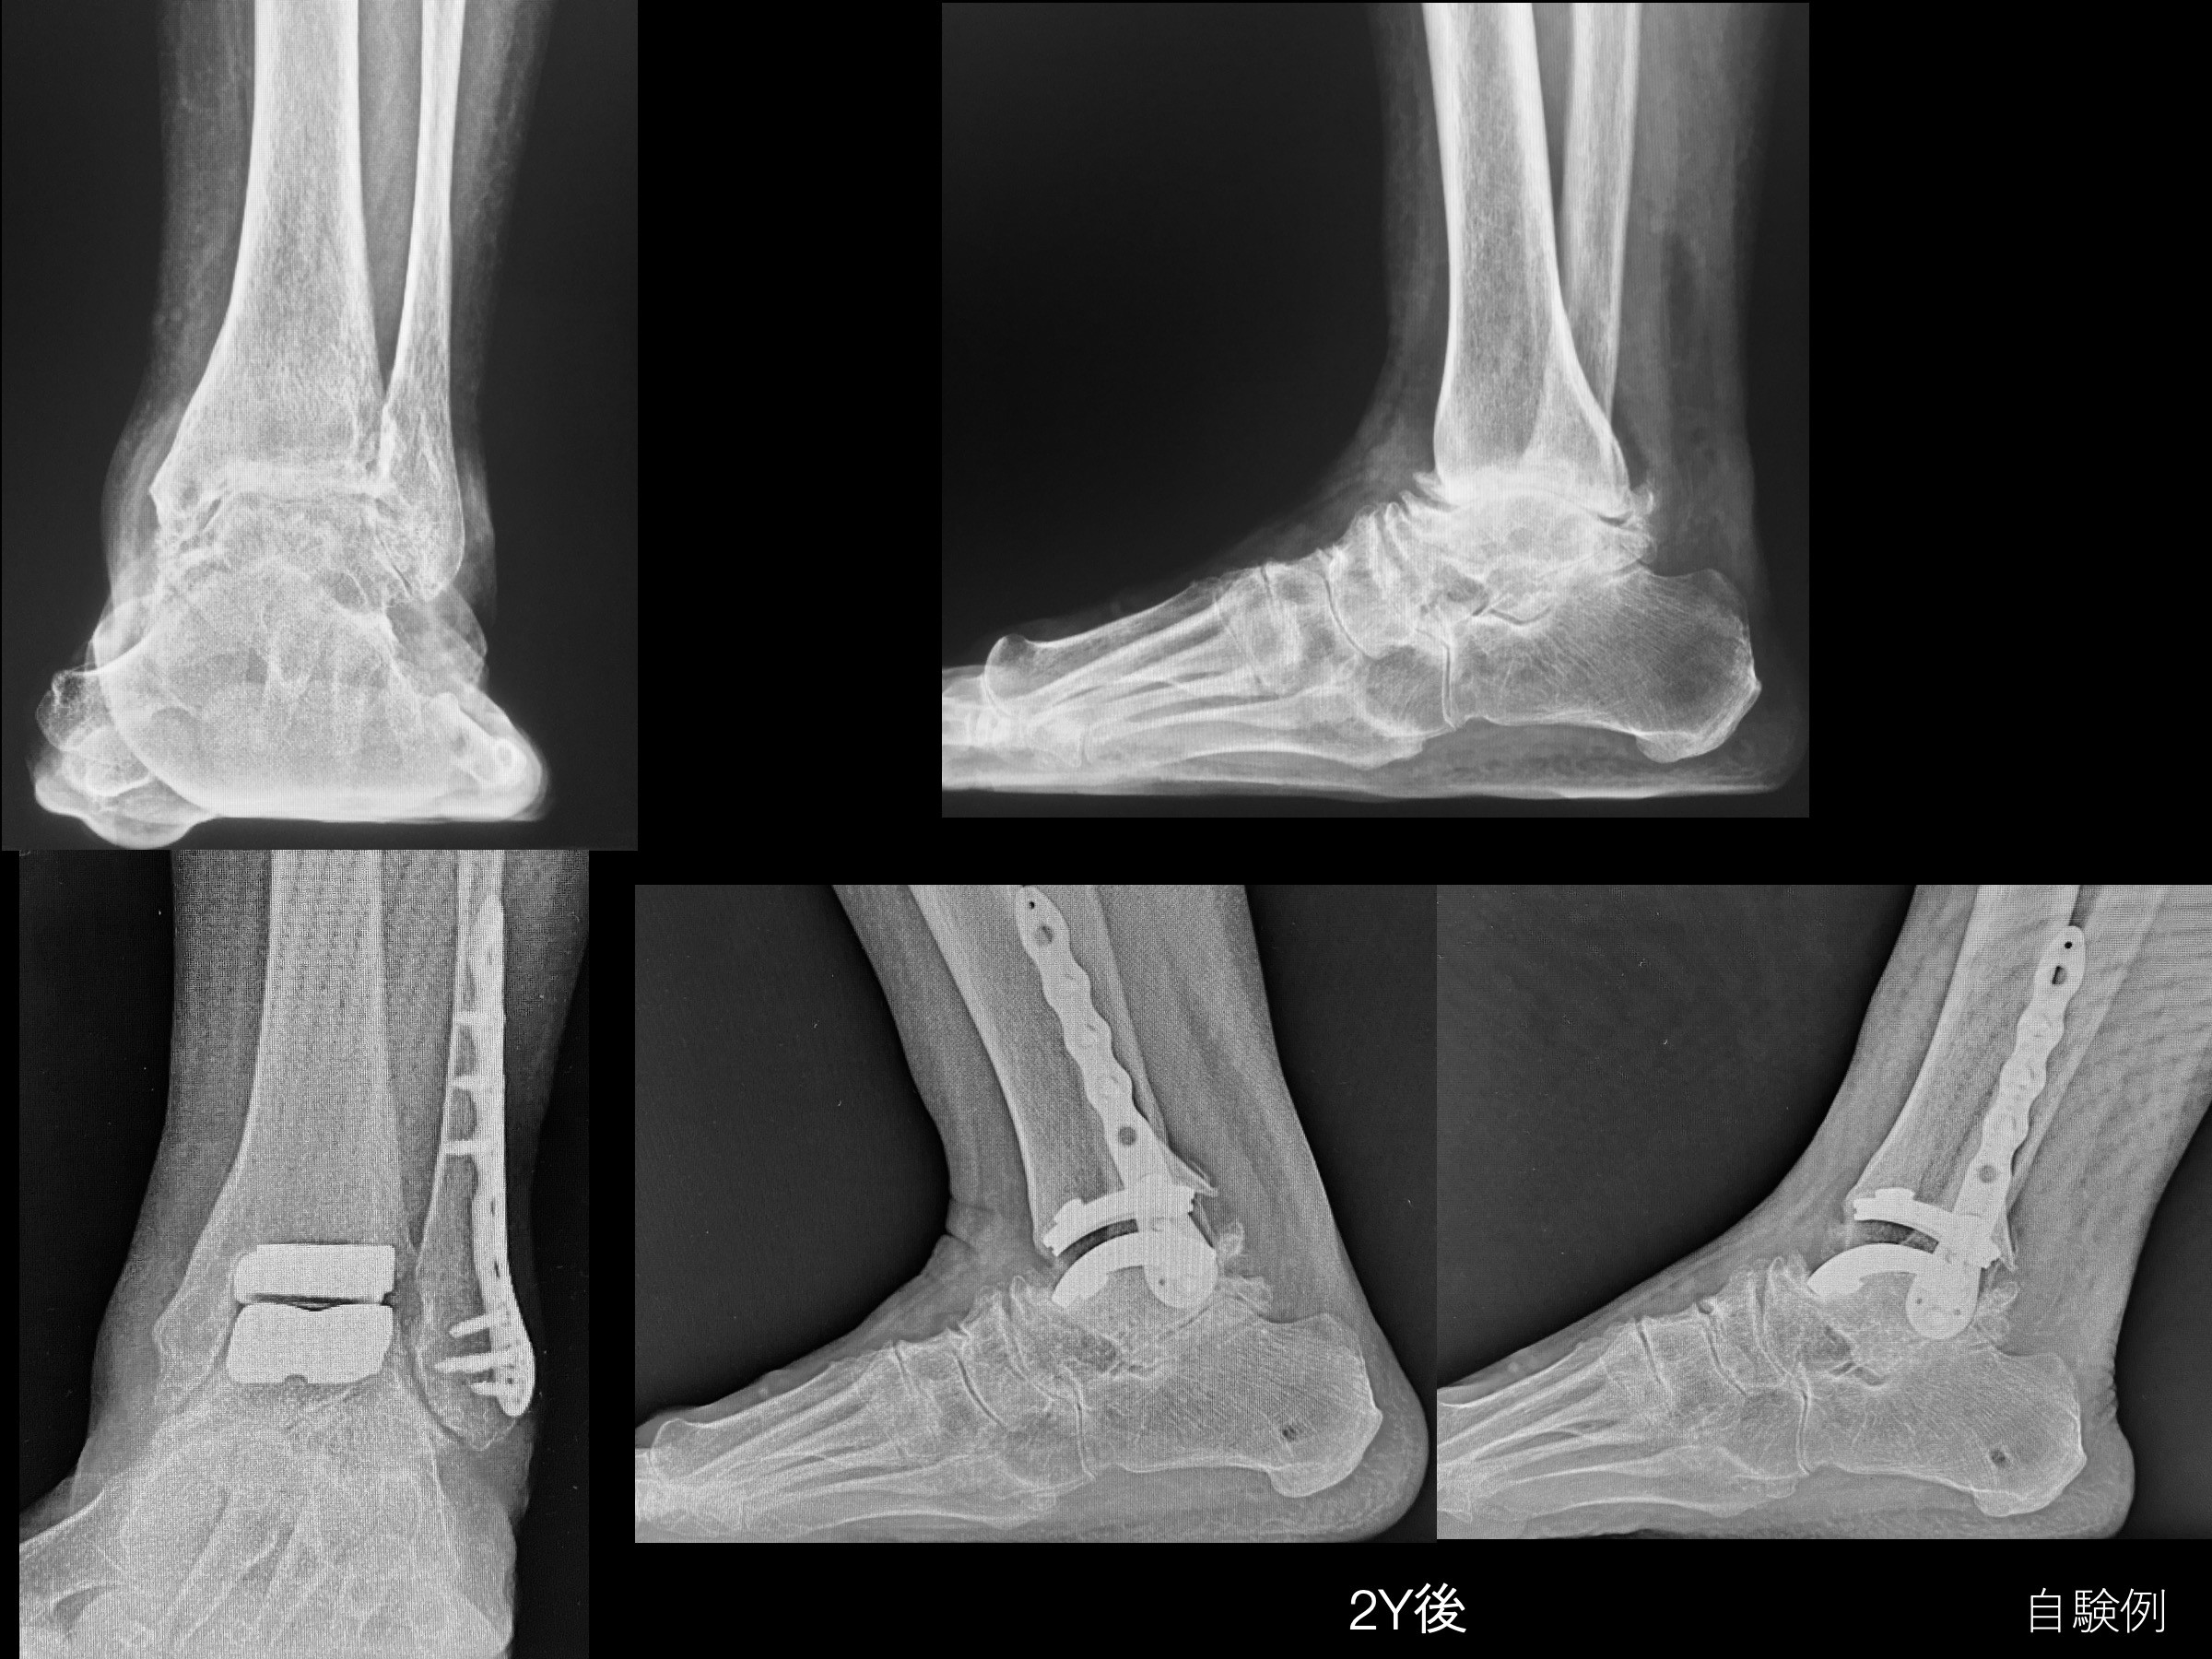

足部と足関節に特化した手術技術を詳細に解説した専門書。- タイトル: 足部・足関節の手術- シリーズ名: 新 Orthopaedic Surgery NEXUS No.16- 出版社: MEDICAL VIEW- 特記事項: Web版あり- 定価: 13,200円ご覧いただきありがとうございます。裁断済み商品になります。そのため、商品の状態は、“全体的に状態が悪い“としていますが、裁断後にスキャンしたのみで、商品の状態は良好です。商品発送後のキャンセルが無いようご確認お願いします。・ローラー痕や少々のページ折れなどあるかもしれませんが、何卒ご容赦ください。・業者により裁断していただいていますが、多少の歪みなどはご承知おきください。・値引き交渉は申し訳ございませんが対応しておりません。よろしくお願いします。